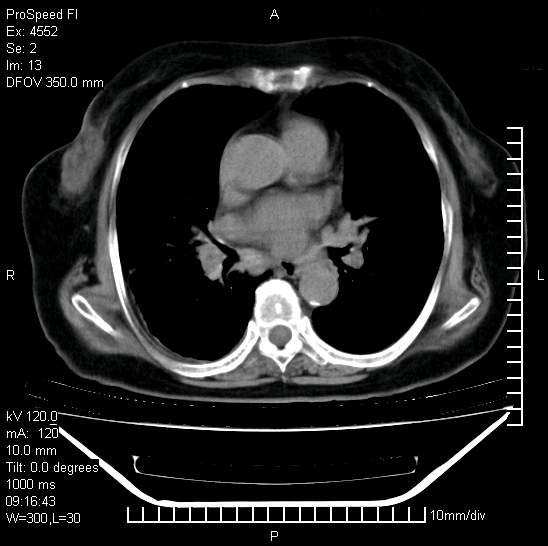

1)两肺结核并感染。2)不排除左肺上叶中央型肺癌并阻塞性肺炎、肺不张可能;建议行纤支镜检查。3)右肺门及纵隔淋巴结肿大。4)双侧胸腔积液。

考虑1双肺tb灶;右下肺支气管壁增后,建议除外占位 3双侧胸腔积液,